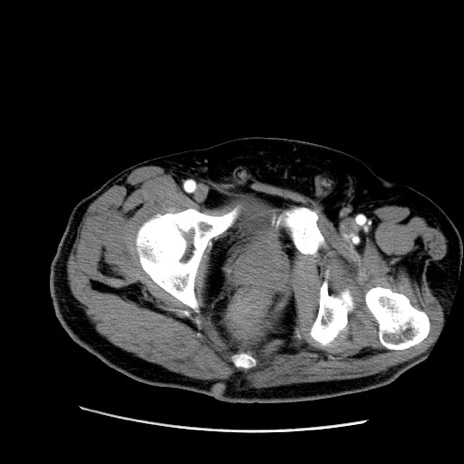

症例22(横断像)

【症例】50歳代男性

【主訴】腹痛

【現病歴】AVMからの被殻出血のため回復期リハ病棟入院中。 本日午後3時頃急に下腹部痛が出現した。

【既往歴】AVM、被殻出血、虫垂炎、高血圧

【身体所見】意識晴明、左半身不全麻痺、会話の理解は良好、36.5°C、腹部:膨隆、全体に板状硬、下腹部正中に圧痛点あり、反跳痛-、筋性防御不明、右下腹部にope scar

【データ】WBC 9400、CRP 0.06